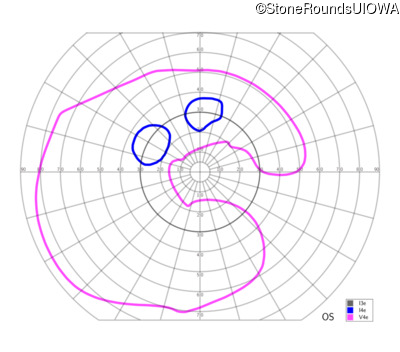

This 81 year old man began using a flashlight to read menus in his 40's. At age 75 his ophthalmologist noticed abnormal fundus findings and referred him to a retina specialist.

| Age at visit: 81 years |

| Age at visit: 82 years |

| Age at visit: 83 years |

| Age at visit: 84 years |

| Age at visit: 85+ (Visit 1) |

| Age at visit: 85+ (Visit 2) |

| OD | OS | ||

|---|---|---|---|